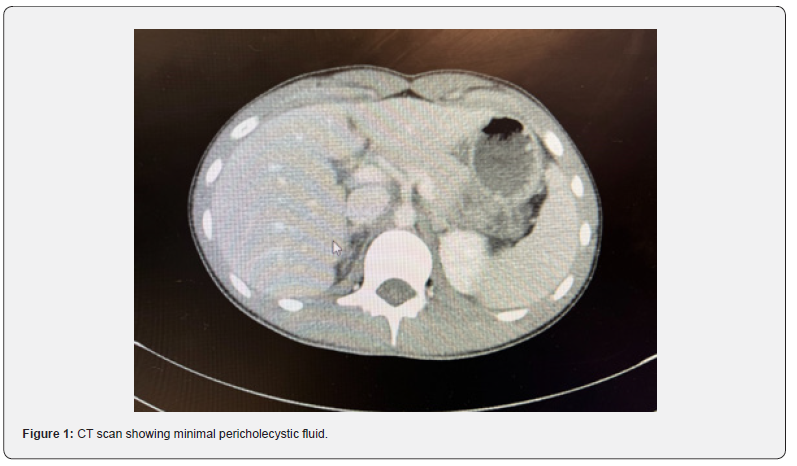

A 15-year-old male with no significant past medical history presented to the Emergency Department (ED) with right upper quadrant pain, nausea, vomiting, and decreased appetite evolving over a duration of 48 hours. On initial presentation, his work-up was remarkable for an elevated total bilirubin of 1.9, unremarkable CBC, and an x-ray showing subtle nodularity in the right colon indicative of possible colitis. Ultrasound was performed and the appendix was not visualized. He was discharged home from the ED with Toradol and Zofran for pain and nausea. He returned the next day with worsening right upper quadrant pain and fever (103 Fahrenheit). His nausea and vomiting had improved, but he continued to have a decrease in appetite. On examination, he was febrile, tachycardic, tachypneic, tender to palpation in the right upper quadrant area, had a negative Murphy’s sign and was jaundiced. Laboratory testing was repeated which showed an increasing total bilirubin from 1.9 to 3.7, mildly elevated ALT of 35, and elevated CRP of 8.5. CBC was unremarkable for leukocytosis, anemia or thrombocytosis. Computed Tomography (CT scan) of the abdomen and pelvis was performed which showed a normal appendix, massive stool burden in the cecum, possible sludge/ stones in the gallbladder with minimal pericholecystic fluid around the tip of the fundus and tip of the liver, with an inability to rule out cholecystitis and a horseshoe kidney with a dilated left renal pelvis (Figure 1). He was given 2 bisacodyl enemas which did improve his pain. A right upper quadrant ultrasound (RUQ) was performed showing gallbladder sludge and pericholecystic edema concerning for acalculous cholecystitis (Figure 2).